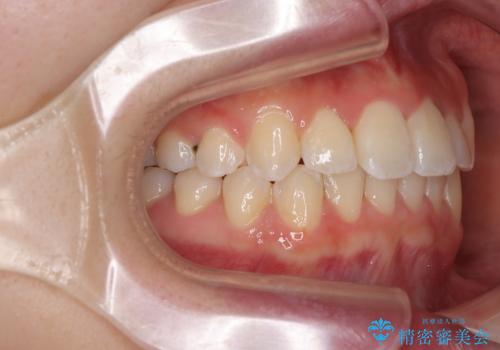

前歯のクロスバイト 裏側に隠れた歯をワイヤー装置で短期間治療

- 上顎前歯のクロスバイトを気にして来院された患者様です。

想定通り、1年強で綺麗に仕上げることができました。